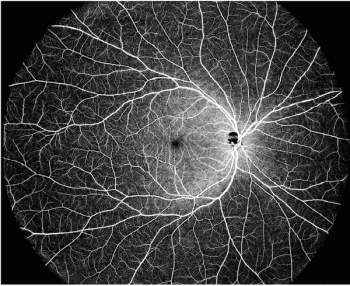

OCT-A angiography can help reveal early neurodegenerative disease signs, offering a noninvasive method for identifying high-risk patients through retinal analysis.

Researchers reveal that retinal microvasculature analysis via OCTA may enhance noninvasive cardiovascular risk assessment, potentially improving coronary artery stenosis detection.

The authors examined vascular and neural structures in the eye, assessing the foveal avascular zone and choroidal thickness